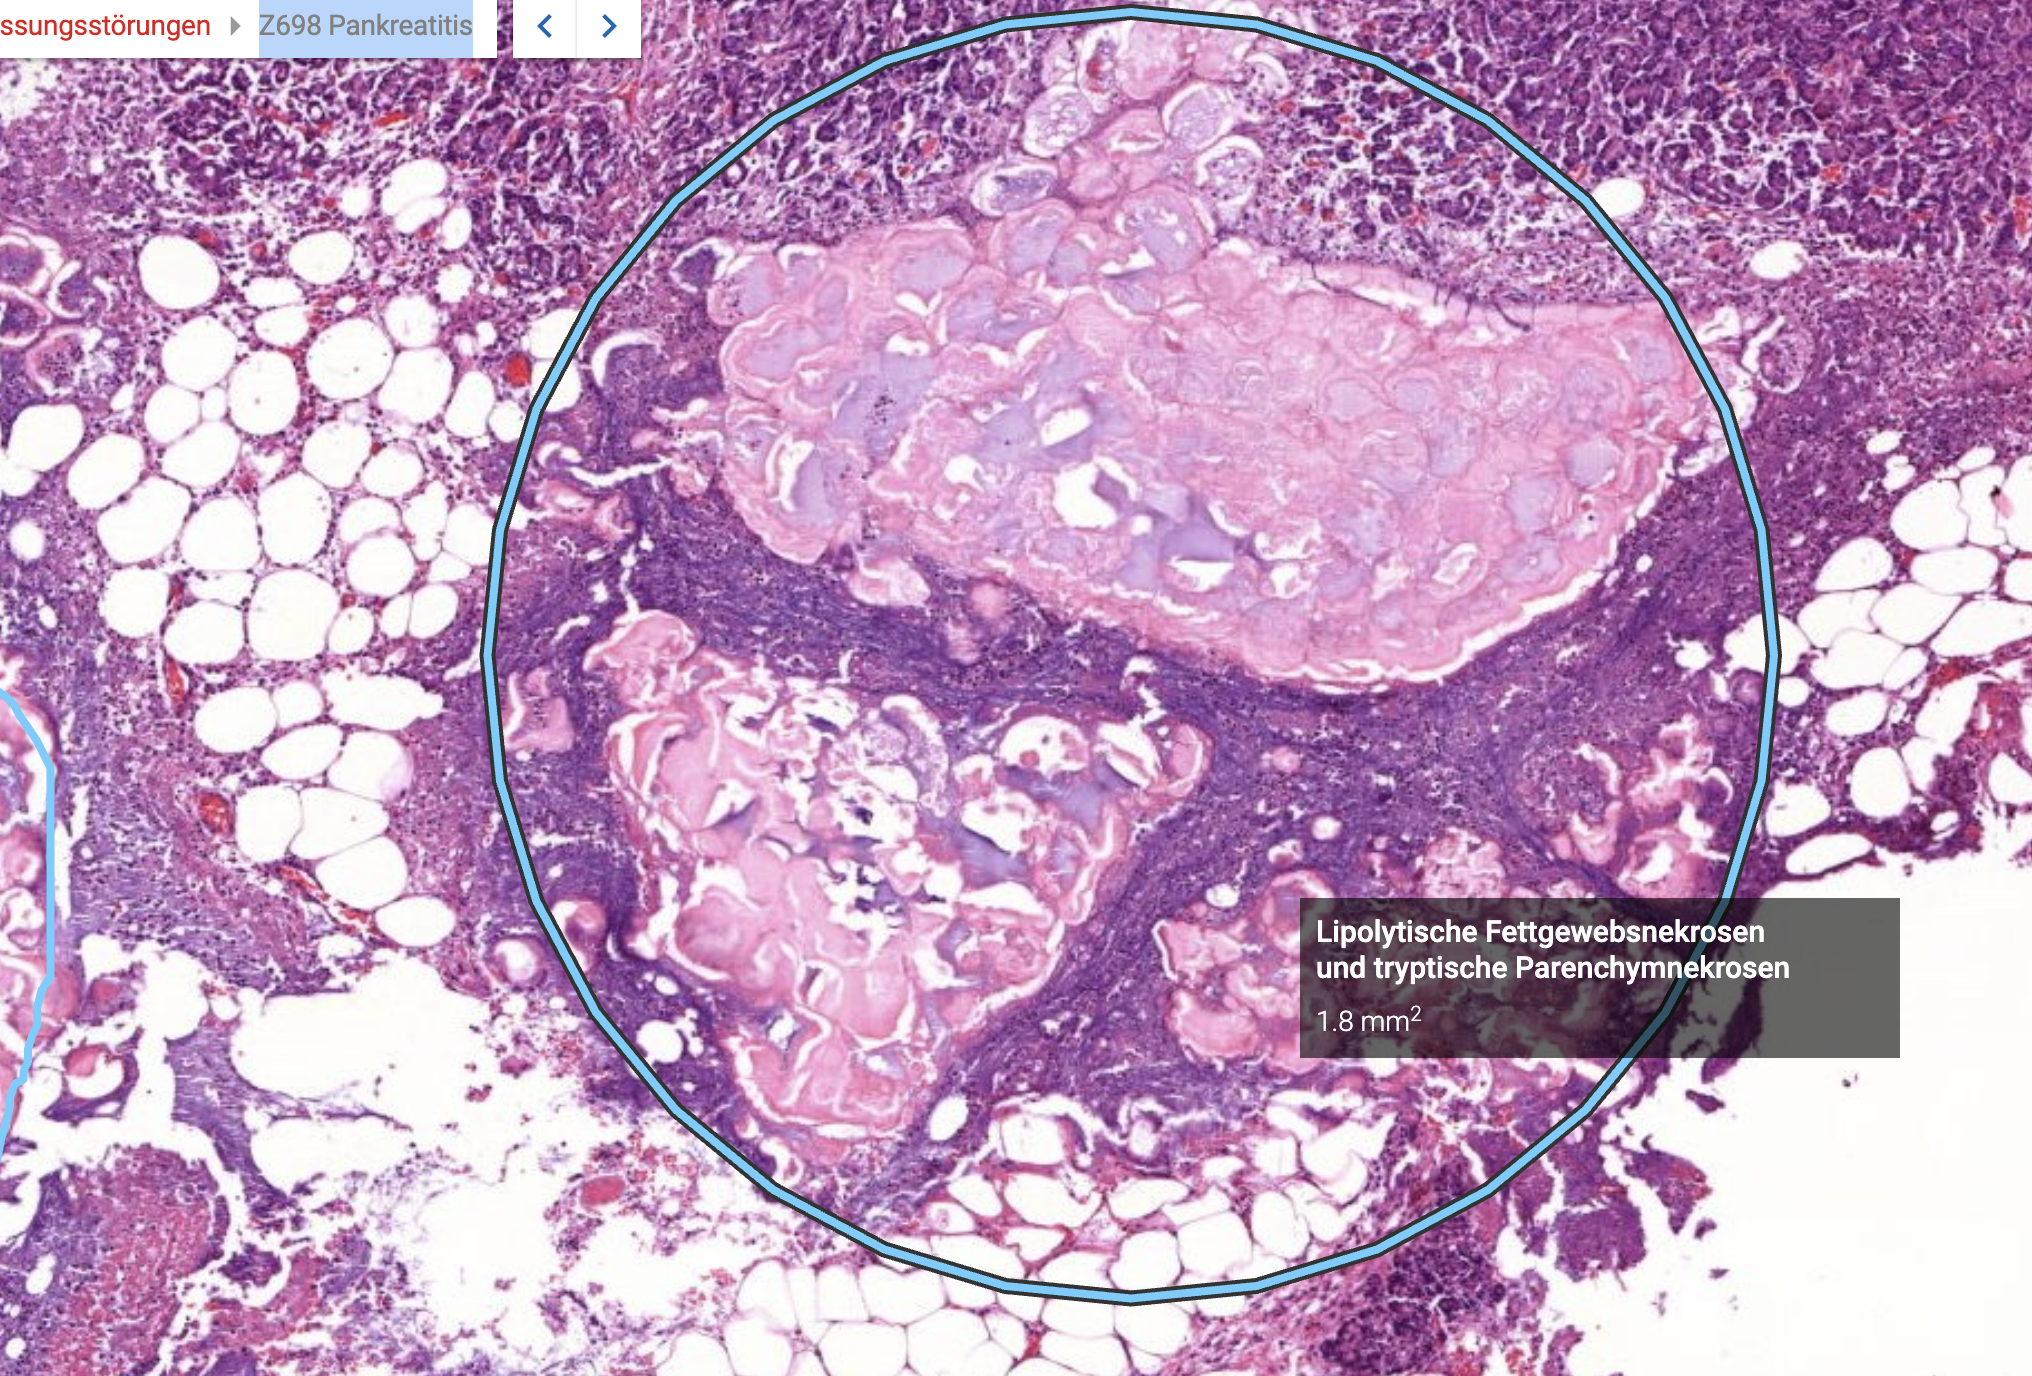

41) Z698 Pankreatitis - Beschreiben Sie die histopathologischen Merkmale.

Zu sehen ist eine Pankreatitis. Hier soll es um besonders um die Fettegwebsnekrose gehen. Eine Lipolytische Fettgewebsnekrose, der Pankreas verdaut sich quasi selber, denn bei der Entzündung des Pankreas werden die Pankreasenzyme die sonst in den Dünndarm geleitet werden

Hier betrifft die Nekrose erstmal nur die Fettzellen, würde aber auch auf das Paarenchym übergehen. Es zeigt sich außerdem Lymphozytäres infiltrat im sinne von neutrophilen Granulaten Histopathologisches Bild: Prostatahyperplasie mit knotiger Architektur Trypsinische Parenchymnekrose Das aktivierte Trypsin führt zur Proteolyse (Eiweißspaltung) des Pankreasparenchyms (der Drüsenzellen, Gefäßwände usw.). Diese Zerstörung des Pankreasgewebes nennt man tryptische Parenchymnekrose. Histopathologisches Bild: Prostatahyperplasie mit knotiger Architektur